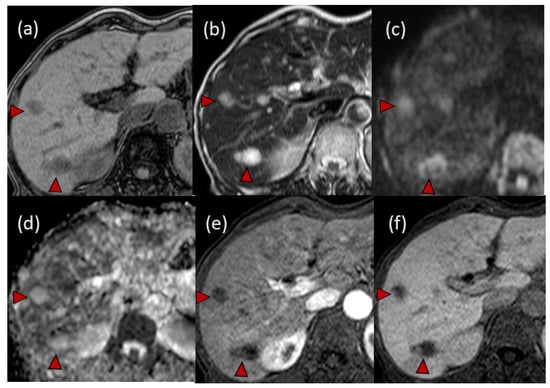

Magnetic resonance imaging (MRI) showed hypo-intensity on T1-weighted imaging, high intensity on T2-weighted imaging, high intensity on diffusion-weighted imaging (DWI) and high values on apparent diffusion coefficient (ADC) maps. Dynamic gadolinium ethoxybenzyl diethylenetriamine pentaacetic acid-enhanced MRI (EOB-MRI) showed hypo-intensity in all (early, late and hepatobiliary) phases (Figure 4).

Figure 4. Findings of magnetic resonance imaging (MRI): (a) hypo-intensity lesions on T1-weighted imaging; (b) high-intensity masses on T2-weighted imaging; (c) high-intensity lesions on diffusion-weighted imaging (DWI); (d) high values on apparent diffusion coefficient (ADC) maps. In the dynamic gadolinium ethoxybenzyl diethylenetriamine pentaacetic acid-enhanced MRI (EOB-MRI), multiple masses were detected as hypo-intensity lesions both in the early phase (e) and hepatobiliary phase (f). Typical tumors are indicated with arrowheads.

In our case, CE-CT showed low-attenuation areas in the center of the tumors (Figure 2). However, at the early vascular phase of CEUS, the tumors were shown as very slight hypoenhancement with some hypervascular parts. These CEUS findings were inconsistent with those of metastatic liver tumors, which have internal necrosis. Malignant lesions reportedly show a high intensity on DWI and hypo-values on ADC because of their high cell density [24,25]. Regarding the MRI findings in our case, the DWI showed high-intensity lesions; however, high values were observed on the ADC maps. In addition, the FDG-PET showed a normal standardized uptake value for the tumors. These results were atypical for metastatic tumors.